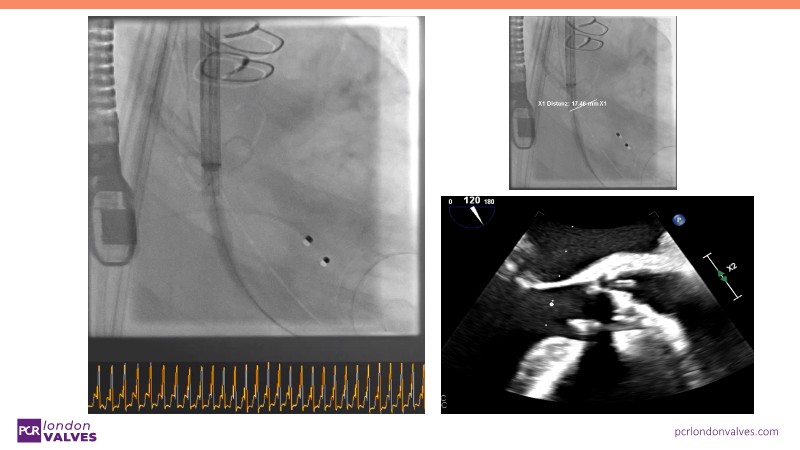

This session offers an in-depth review of complex TAVI cases, focusing on overcoming clinical challenges and achieving optimal outcomes with the Evolut FX+ device. Participants will learn about recent advances in TAVI indications for younger and asymptomatic patients, strategies for managing TAV in surgical aortic valve (SAV) patients including redo TAVI, and explore technological innovations designed to address complex anatomical scenarios.

- To learn how to anticipate the challenges of TAV in SAV and how to perform a redo TAVI

- To discern the latest technological evolutions that enable the treatment of patients with complex anatomy